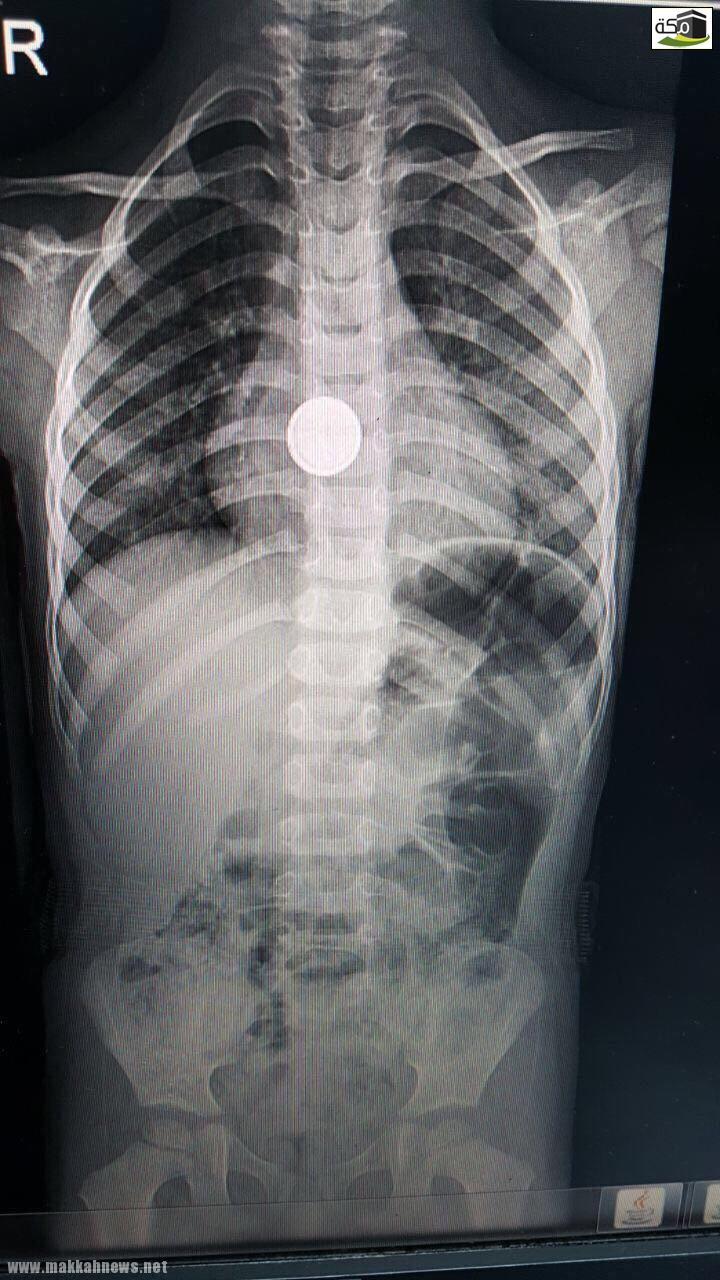

فريق طبي بـ ولادة مكة ينجح في إنقاذ طفلين إبتلعا بطاريتين حارقتين

مكة – حزام الزهراني بفضل من الله تمكن فريق طبي بمستشفى الولادة والأطفال بمكة المكرمة من إنقاذ طفلين تتراوح أعمارهما…